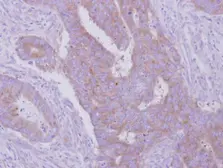

Images